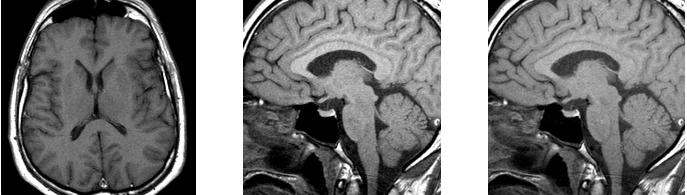

从左到右依次为:

TR 582 ms,翻转 90o \\ TR 582 ms,翻转 69o \\ TR 400 ms,翻转 80o